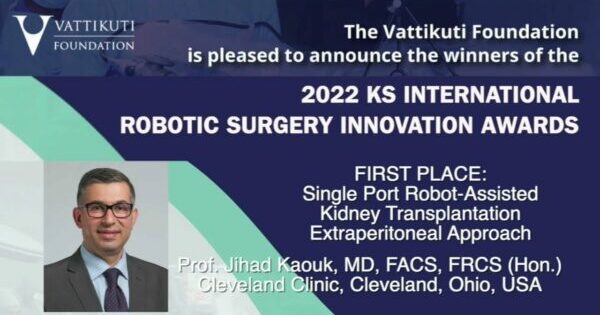

Single Port Robot-Assisted Kidney Transplantation: Extraperitoneal Approach

2022 KS International Robotic Surgery Innovation Awards Live Program